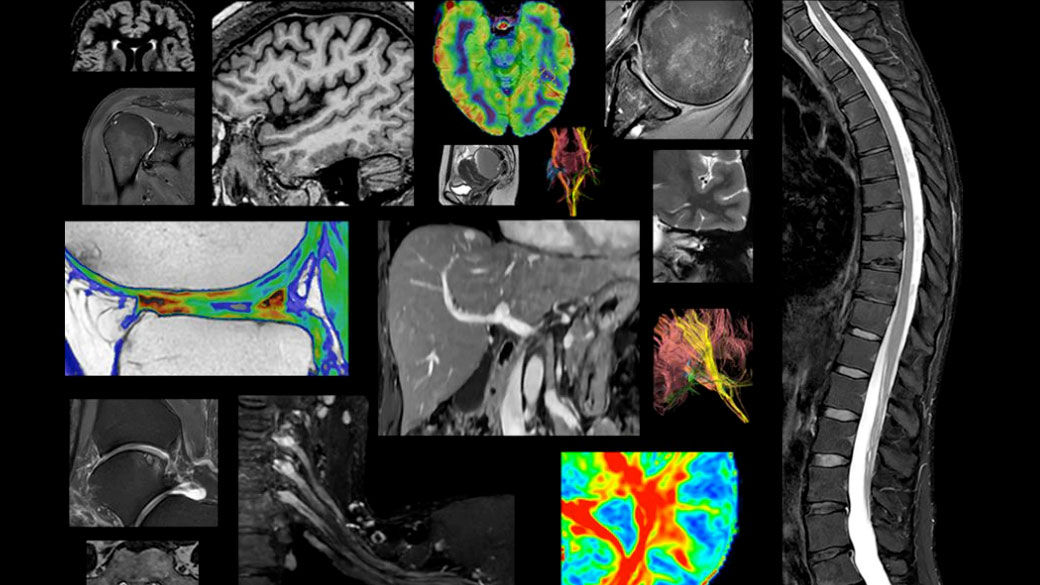

With UltraG gradients, the SIGNA™ 7T MRI scanner delivers superior contrast and SNR performance for improved diagnostic confidence, all with familiar state-of-the-art applications.

Designed to overcome the limitations for many of today’s clinical MR systems, the SIGNA™ 7T is a powerful new platform for advancing neurological research and clinical translation. Approximately five times more powerful than most clinical systems, SIGNA™ 7T is designed to detect subtle structures that may be significant for clinicians and researchers alike. Boost advanced applications with GE HealthCare's most powerful whole-body gradient platform to date, delivering exceptional resolution and contrast-to-noise ratio.

Uncover new contrasts, such as Quantitative Susceptibility Mapping (QSM), for advancing neurological disorder research. Explore novel biomarkers for ischemic stroke characterization and uncover subtle structures with ultra-high resolution imaging with our SIGNA 7T platform.